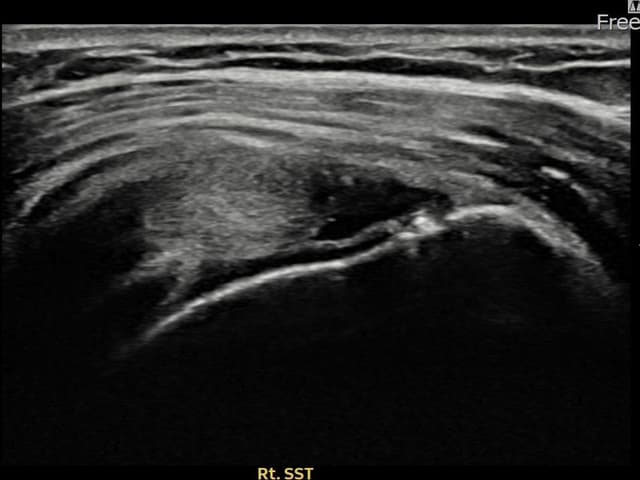

[経過期間: 23.09.19~23.11.21]

[縫縮術] 超音波検査にて右 棘上筋腱 関節面側部分断裂(9mm × 4mm (腱厚の約38%欠損))を確認。縫縮術施行後、腱の連続性が回復し、日常生活に復帰されました。